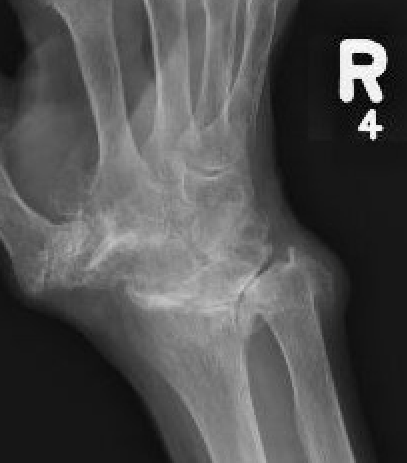

SLAC wrist